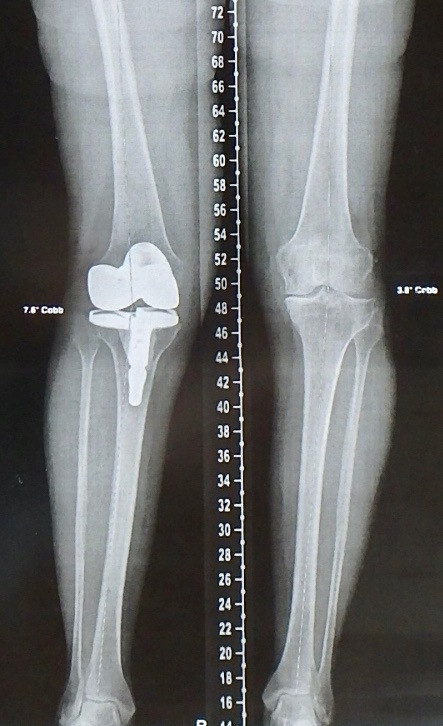

Radio des deux genoux après Prothèse Totale du Genou droit de Simone (radio prise le 14 décembre 2017, 3 mois après l’opération).

Xray of Simone’s Knees after her right Knee Total Prothesis (radio taken on 14th December 2017, 3 months after the operation).